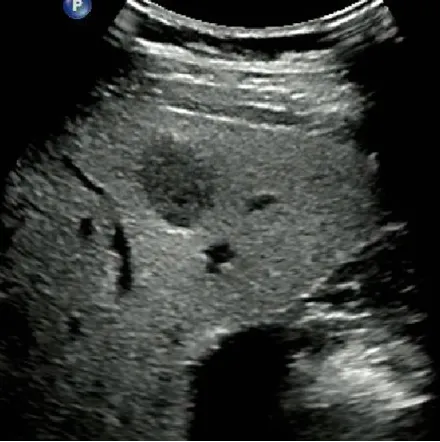

肝细胞癌

定义

是肝内最常见的原发性恶性肿瘤,其恶性程度高、预后差,中老年男性多见。

病理分型

● 巨块型:为单个圆形巨大肿瘤,或由数个癌结节融合而成。癌肿直径大于5cm,少数达10cm以上。

超声表现

● 巨块型肝癌:体积较大,>5cm

高回声多见,多伴有液化坏死

无纤维包膜(浸润性生长)

易并发肝破裂出血

● CDFI:大多数为富血供肿瘤。

肿瘤区域内有丰富的彩色血流信号。

高速、高阻。